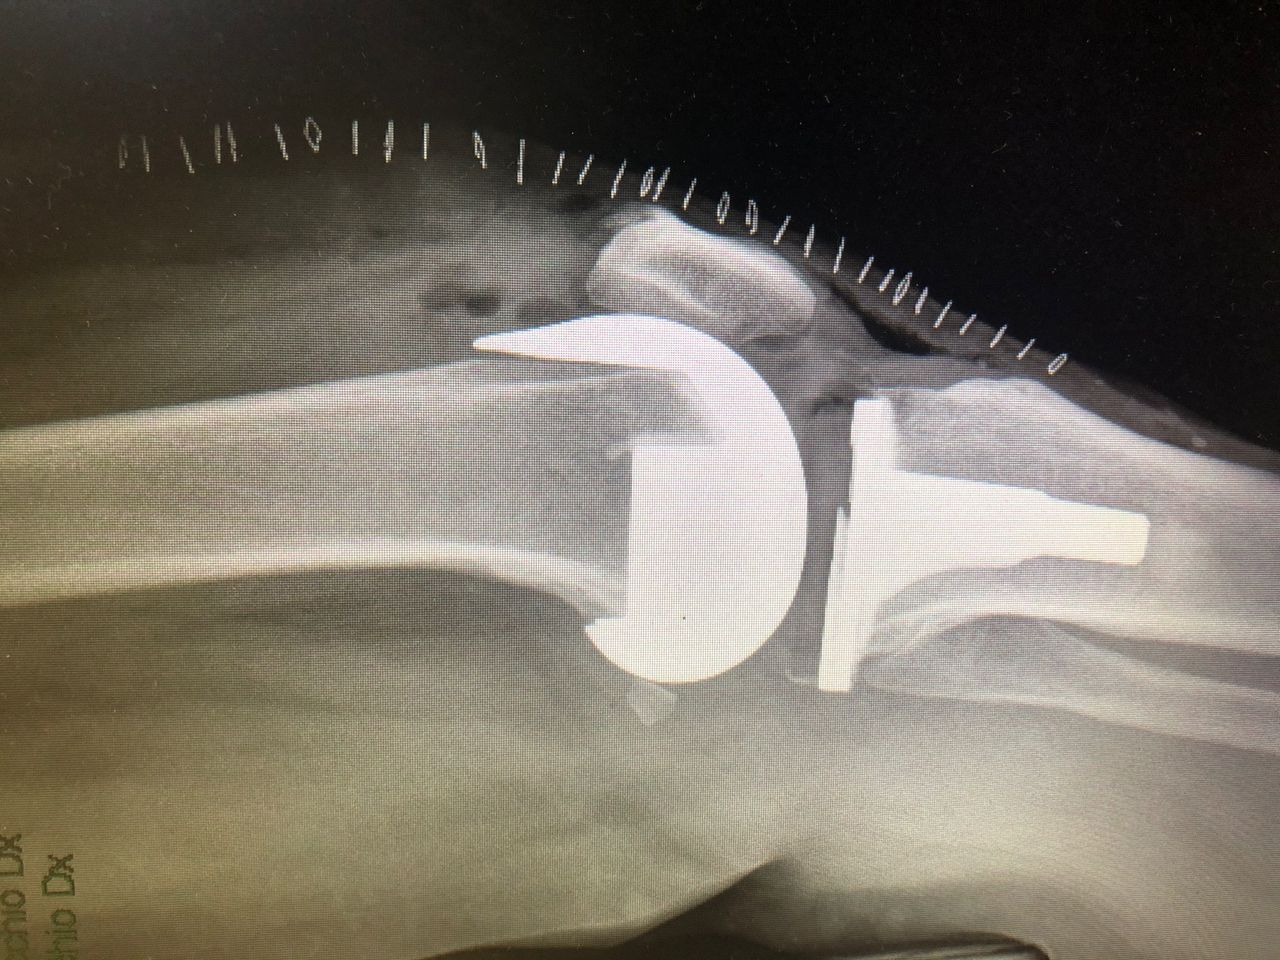

Sono specializzato nell'impianto di protesi di ginocchio ed anca in caso di patologie degenerative artritiche o necrotiche. Utilizzo protesi di ultima generazione, le protesi di ginocchio vengono applicate utilizzando una maschera creata su misura per ogni paziente, quelle di anca sono studiate per ridurre al minimo il rischio di lussazione (principale complicazione di questo tipo di intervento).